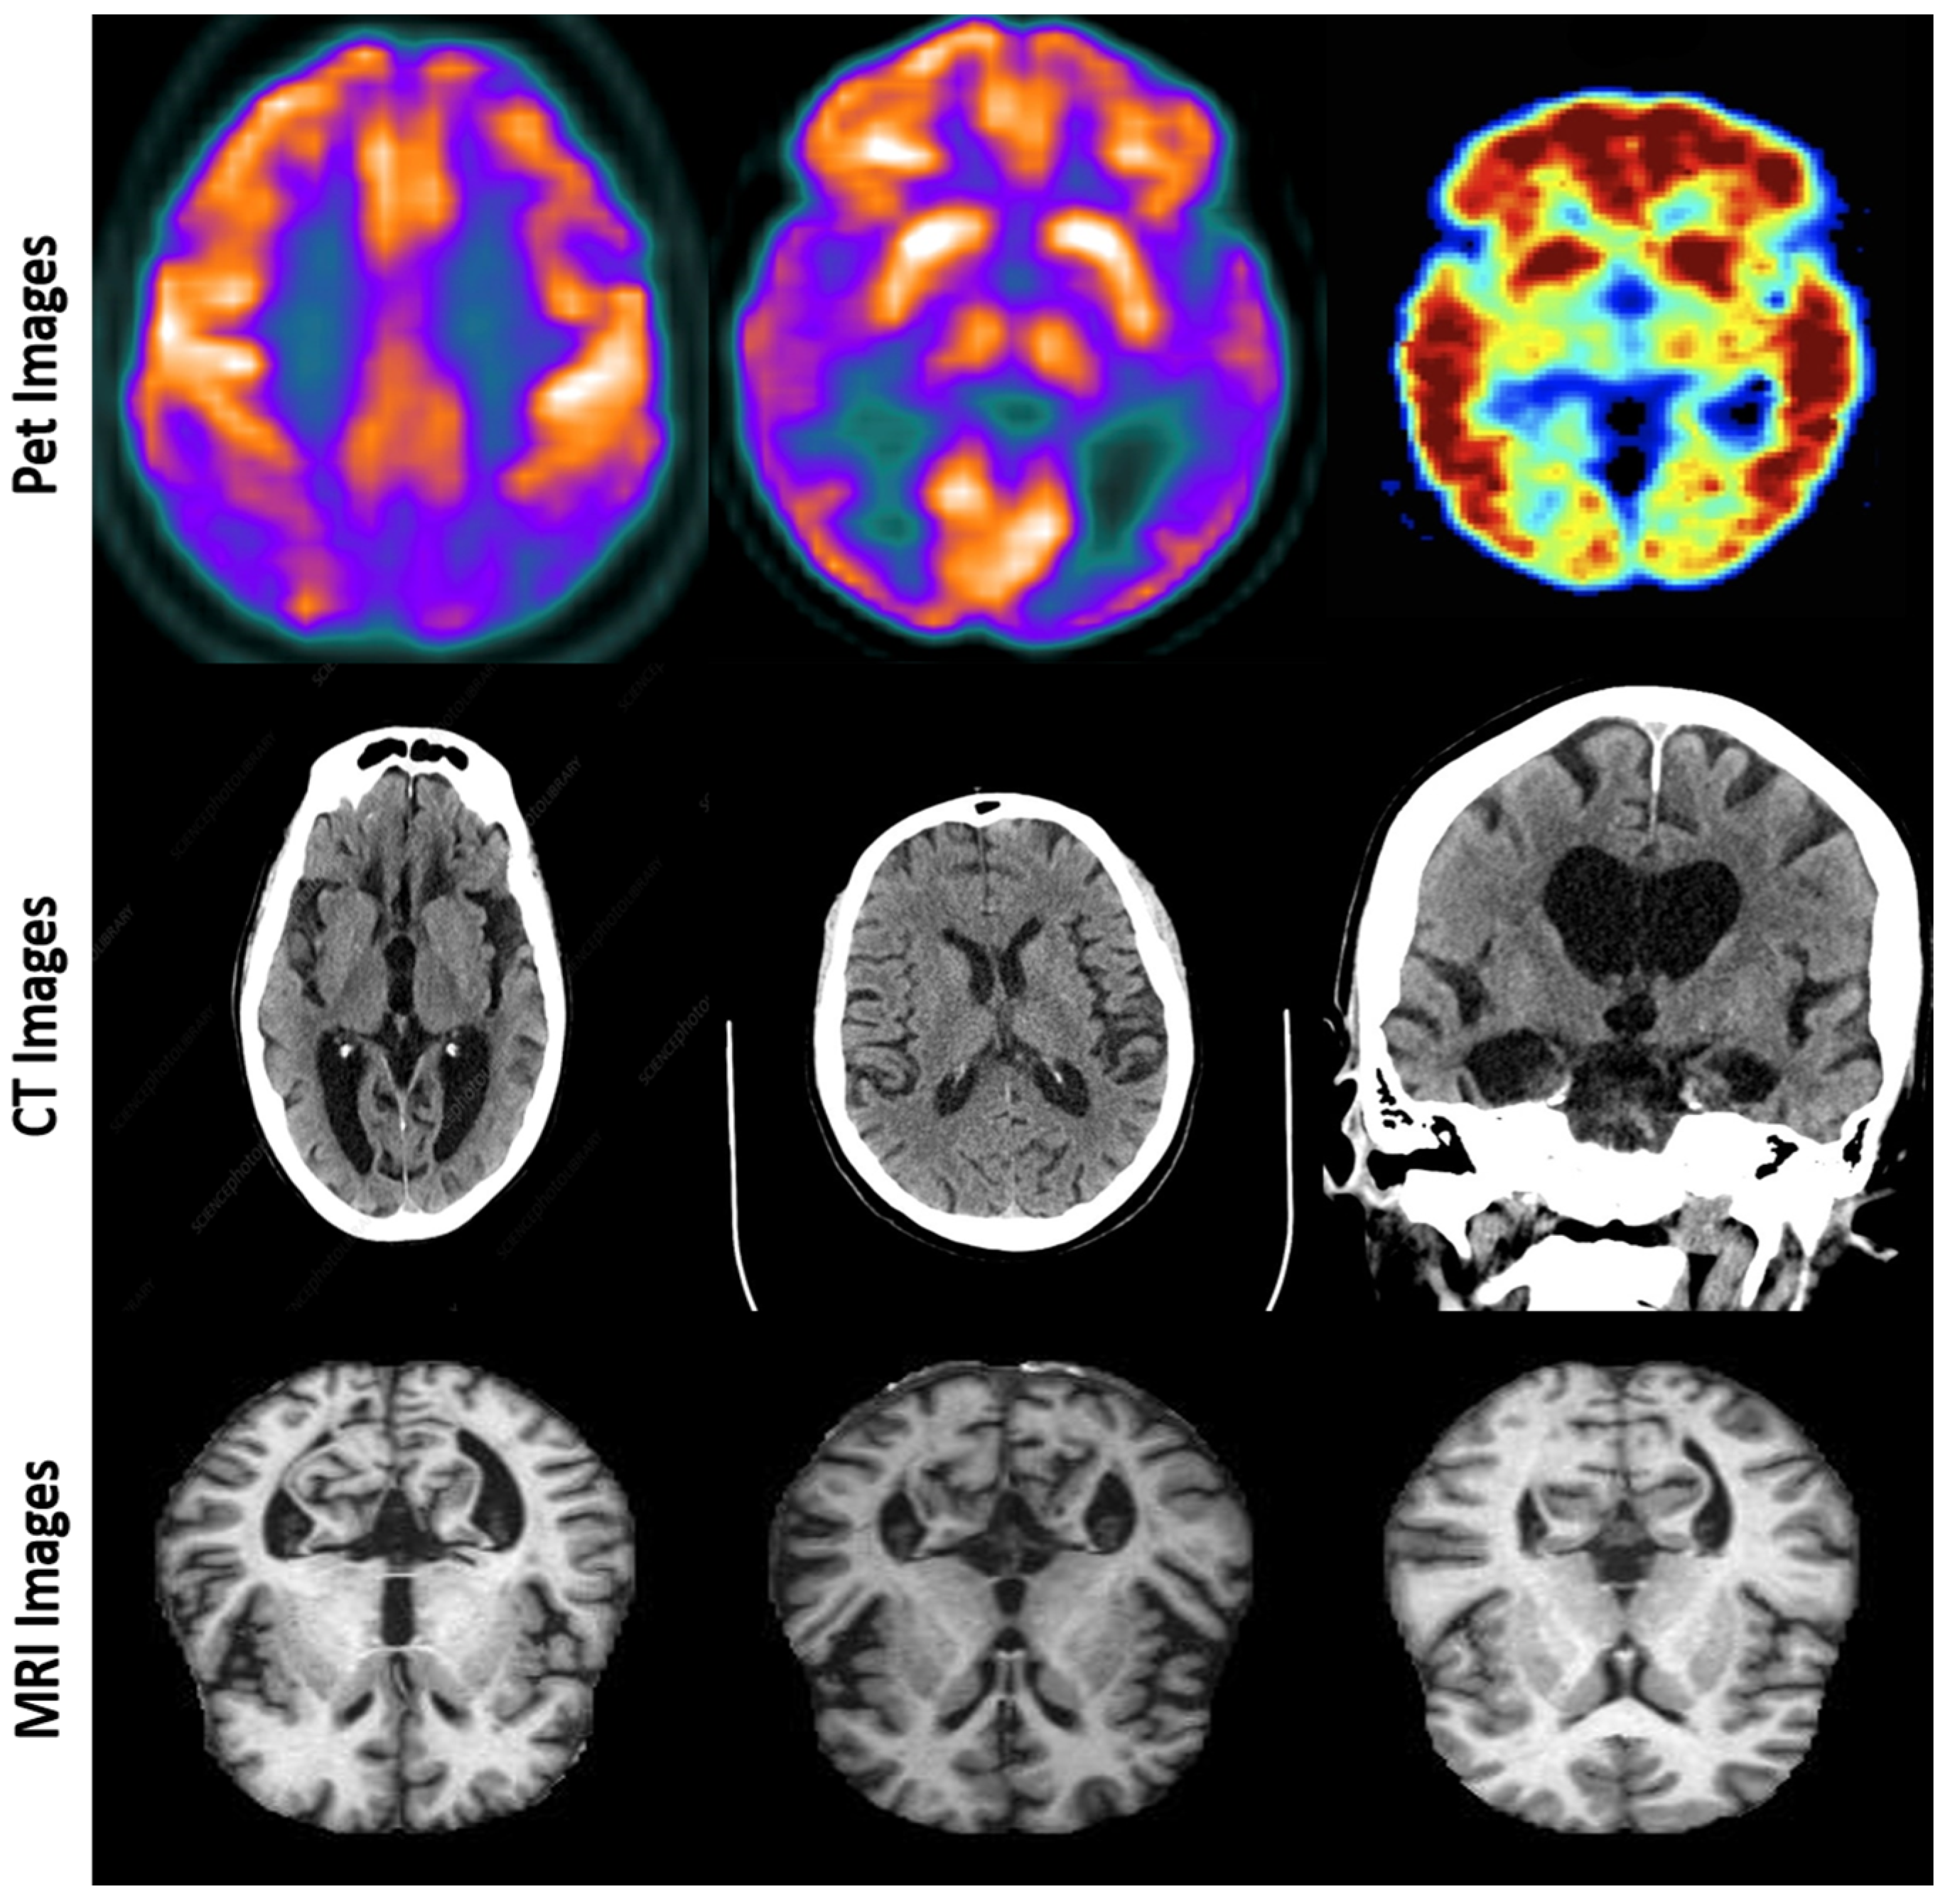

The effectiveness of FusionNet was assessed using a comprehensive dataset compiled from various sources, including the ADNI and OASIS [24,25] datasets. These datasets encompass a broad spectrum of Alzheimer’s disease progression, from normal cognitive function to severe Alzheimer’s disease stages, including MCI, which often precedes Alzheimer’s. The datasets were divided into training, validation, and test sets, ensuring a balanced representation across all classes Figure 2.

Figure 2. Representative multi-modal imaging data: PET, CT, and MRI scans for Alzheimer’s disease diagnosis.